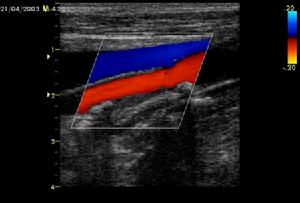

圖23.繼發纖溶期 臨床出血廣泛且嚴重,主因消耗大量凝血因子,血液處於低凝狀態,且繼發纖溶亢進。FDP 抑制血小板聚集並有抗凝作用,加重出血,而休克、酸中毒也使疾病繼續惡化。